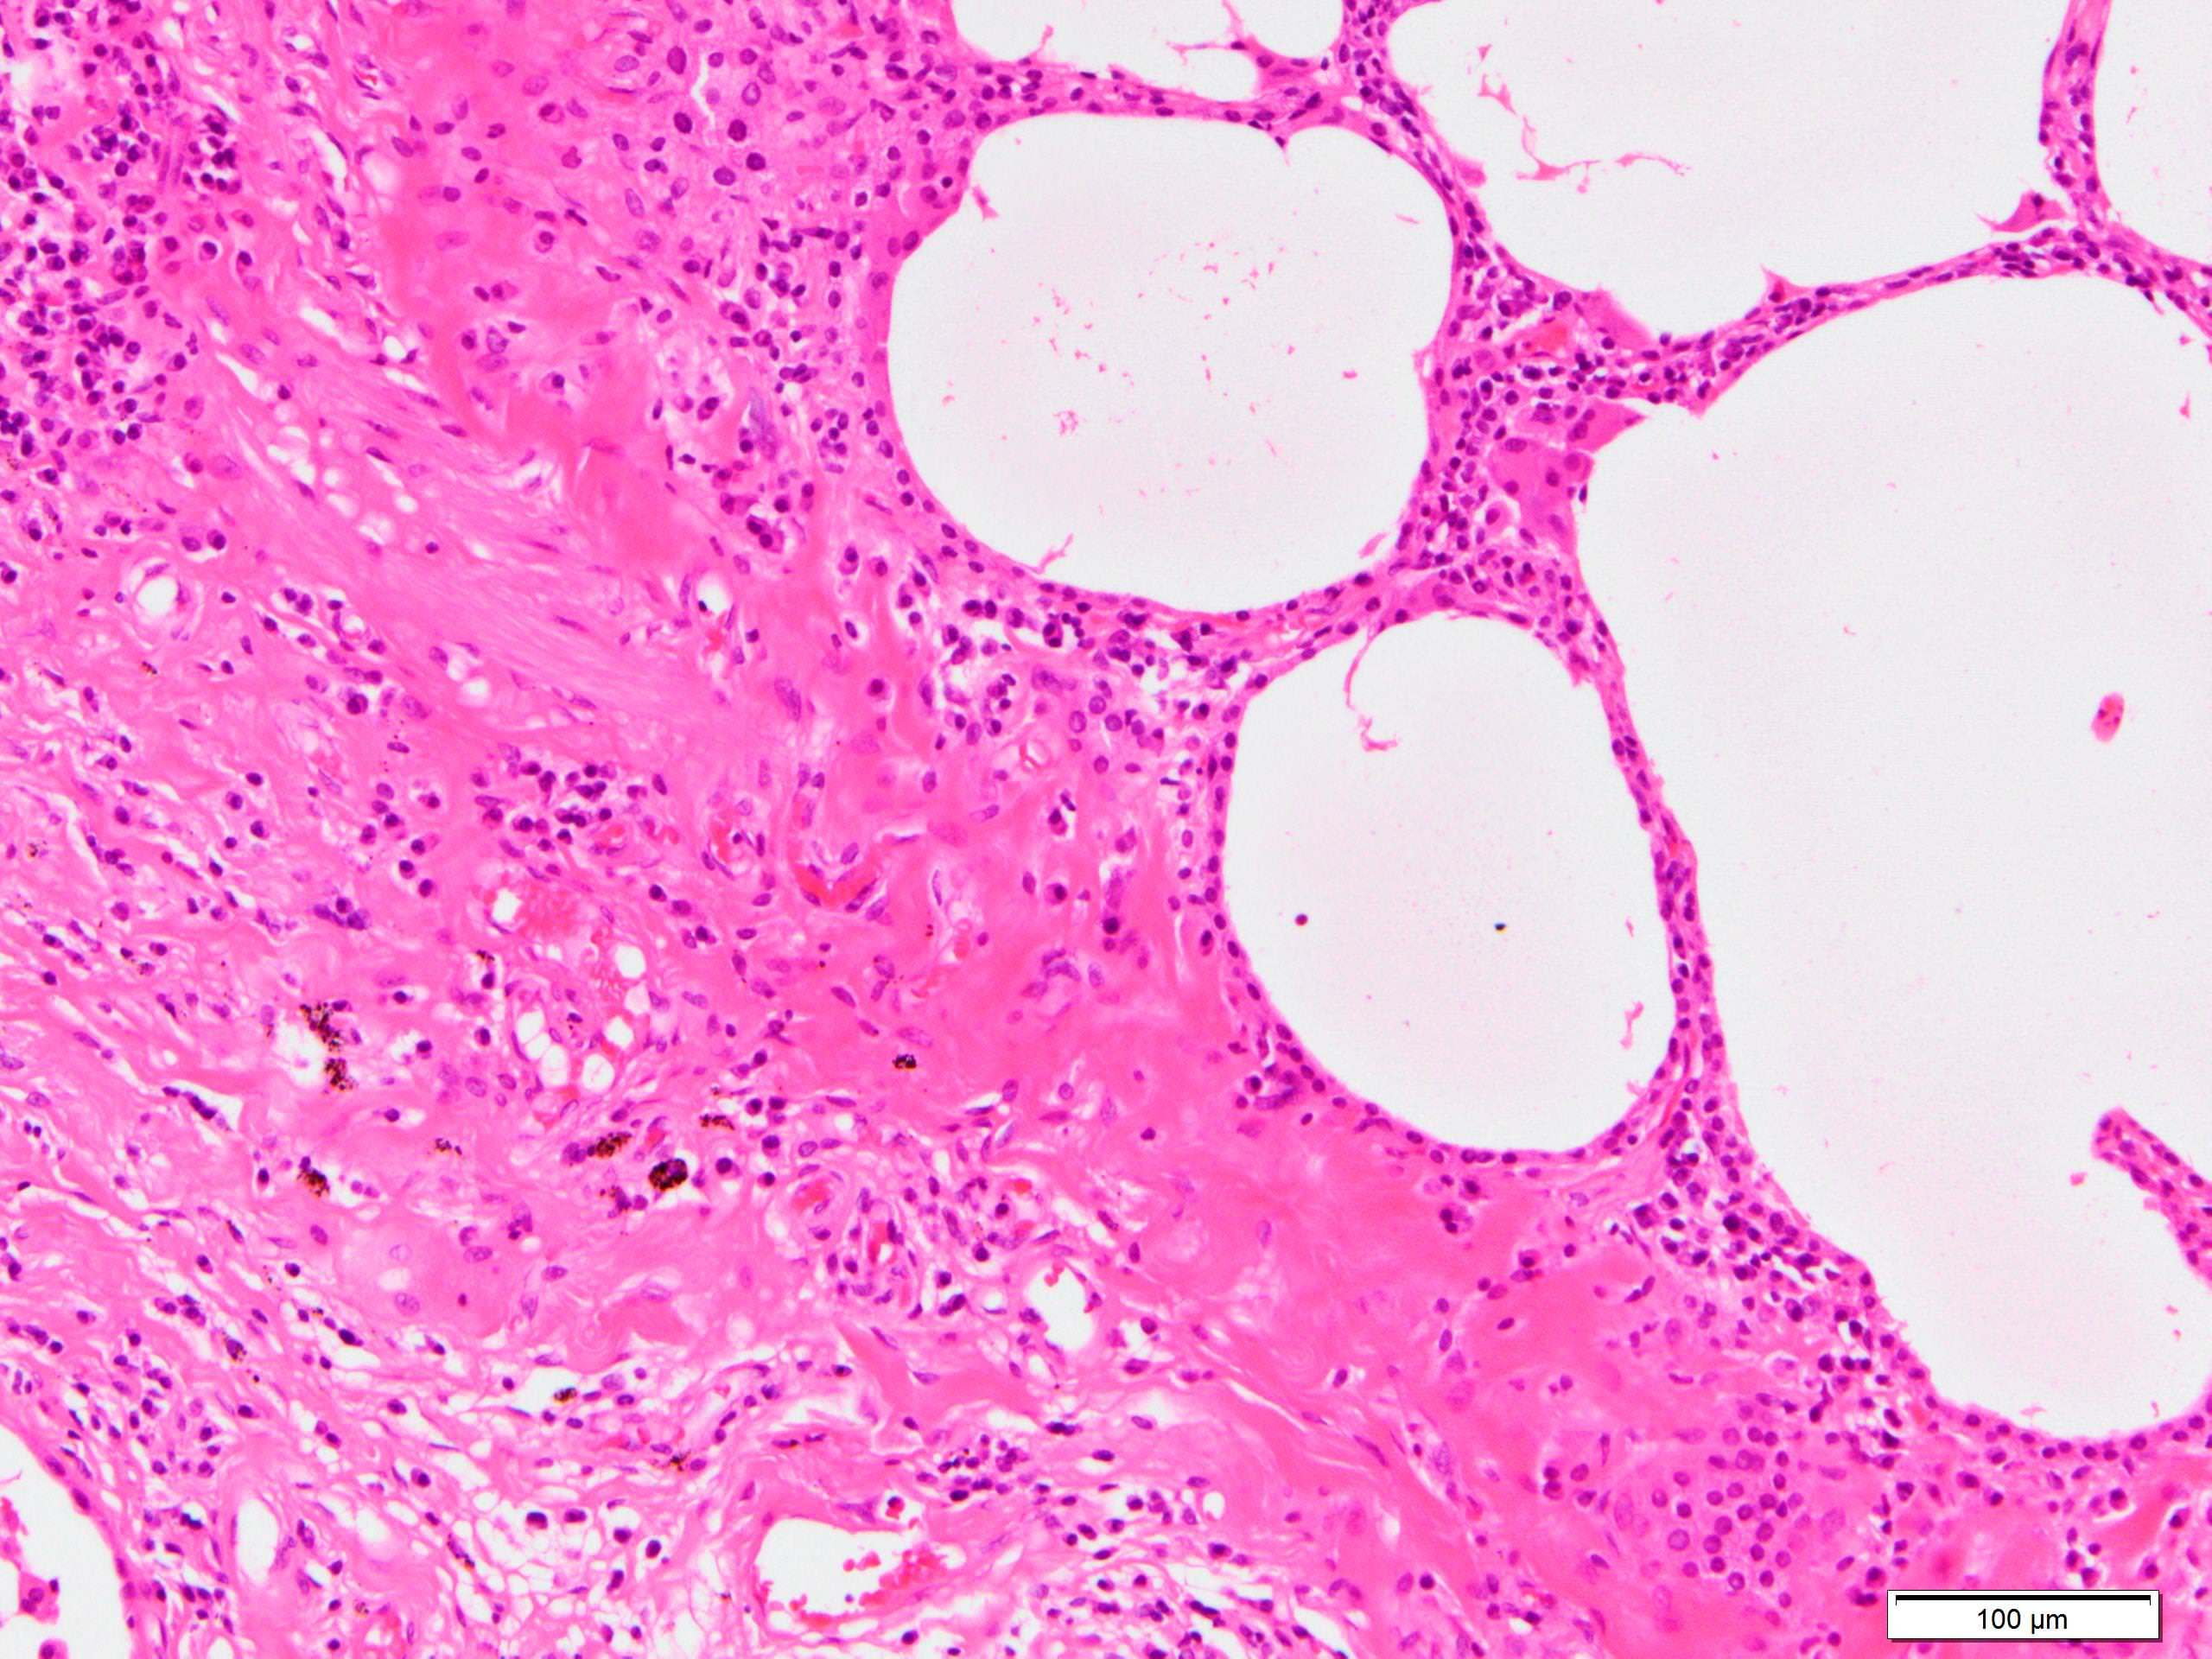

Microscopic (histologic) description

- Since there are few specific findings for NSIP pattern, it is essential to exclude other lung diseases on histology (Am J Respir Crit Care Med 2008;177:1338)

- Characteristic findings of NSIP pattern

- Diffuse and uniform inflammation ("temporal homogeneity") on low power of alveolar wall, bronchovascular bundles and pleura

- Cellular or fibrotic change

- Lymphocytic or plasmacytic infiltration

- Loose fibrosis

- Lung architecture is frequently preserved

- "Cellular NSIP" or "fibrotic NSIP" can be stated specifically in pathologist report

- Diffuse and uniform inflammation ("temporal homogeneity") on low power of alveolar wall, bronchovascular bundles and pleura

- Dense perivascular collagen

- It is quite rare to see pure NSIP on histology - typically there are focal findings of other interstitial lung disease (Histopathology 2014;65:549)

- Pertinent negative findings (Am J Respir Crit Care Med 2008;177:1338)

- UIP-like change

- Marked architectural distortion

- Dense fibrosis with smooth muscle hyperplasia or elastosis

- Fibroblastic foci

- Honeycomb change

Microscopic (histologic) images

Scroll to see all images.

Contributed by Akira Yoshikawa, M.D.

Images hosted on other servers:

Contributed by Akira Yoshikawa, M.D.

Images hosted on other servers: